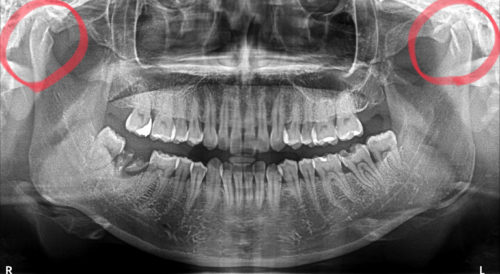

この方は、20代女性ですが、顎の関節が、左右とも、重度に吸収しています

こうなると、完全に治るのは難しい、と言われています